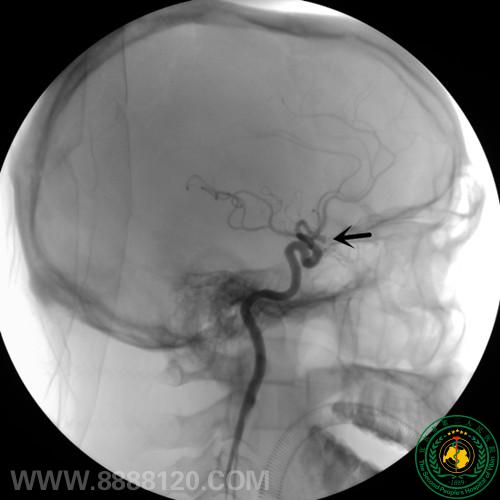

我科成功完成1例复杂前交通动脉瘤的介入治疗

我科成功完成1例复杂前交通动脉瘤的介入治疗9454